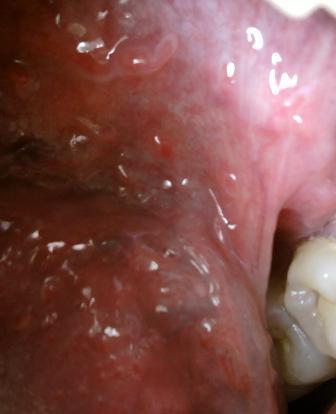

石家庄九州皮肤病医院 > 尖锐湿疣 > > > 尖锐湿疣怎么治疗效果好现在患上尖锐湿疣性病的人已经是越来越多了,患病之后及时就诊是很关键的,切忌不可以拖延治疗,任何疾病只有经过正规的治疗才能达到理想的治疗效果,希望大家应该认识到这一点。

尖锐湿疣怎么治疗效果好现在医学在进步,治疗尖锐湿疣的方法也是比较多的,在这里温馨提示大家在患病之后不可以盲目,选择适合自身病情的治疗方法,坚持治疗对于疾病的治疗和康复至关重要。患病之后,应该认真对待自身健康。患病治疗期间应该避免性生活。患者要正视自身病情,要坦然接受事实,不可以出现消极的情绪,积极乐观的心态,没可以对疾病的治疗起到积极的辅助作用。